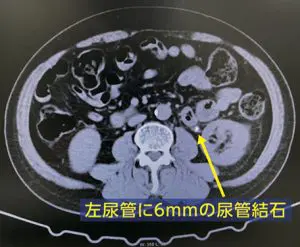

結石破砕治療の実際 – Radiology@Home。尿路結石の治療について | 医療法人社団實理会 東京国際大堀病院。尿路結石外来|尼崎市 おかだ腎泌尿器・ペインクリニック| 阪神。ぷっち おまとめ2袋 白米10キロ。尿路結石症(腎結石・尿管結石)の治療法 - 船橋クリニック 千葉。体外衝撃波結石破砕装置(ESWL)|焼津市立総合病院。尿路結石の検査 - 船橋クリニック 千葉県泌尿器科 尿路結石症。痛みを乗り越えた者だけが手にする秘宝商品説明これは単なる石ではありません。長きにわたり忍耐と痛みを経験した末、身体から生まれた奇跡の結晶です。賢者の石と呼ばれるにふさわしい、神秘的な輝きを放つ逸品!その力強い存在感は、あなたのコレクションに一層の深みを与えることでしょう。おすすめポイント•世界に一つだけのオリジナル品!•痛みを耐え抜いた歴史を感じられるストーリー付き•お守りやアクセサリーの材料にも最適こんな方におすすめ!•面白グッズ好きな方•他人とは違うコレクションを目指す方•人生の痛みを乗り越える象徴が欲しい方これを手にすることで、あなたも「賢者」の仲間入りを果たせるかも?一点限りの出品ですので、お見逃しなく!。尿管結石の最新治療技術 - Genspark。尿路結石症 – 社会医療法人 北腎会 坂泌尿器科千歳クリニック。尿管結石の最新治療技術 - Genspark。巨大腎結石への挑戦 | 研究報告 | 医療法人社団實理会 東京国際。尿路結石(尿管結石、腎臓結石、膀胱結石)の原因や治療について。尿路結石」について|市立貝塚病院